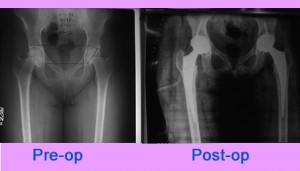

Bilateral Total Hip Replacement

31 years old lady presented to us with pain in both hips and difficulty in walking. She is a known case of systemic lupus erythematous ( SLE) with avascular necrosis of both hips. On examination she had gross restriction of movements of both hips.

She had undergone uncemented Total Hip Replacement ... Read more..